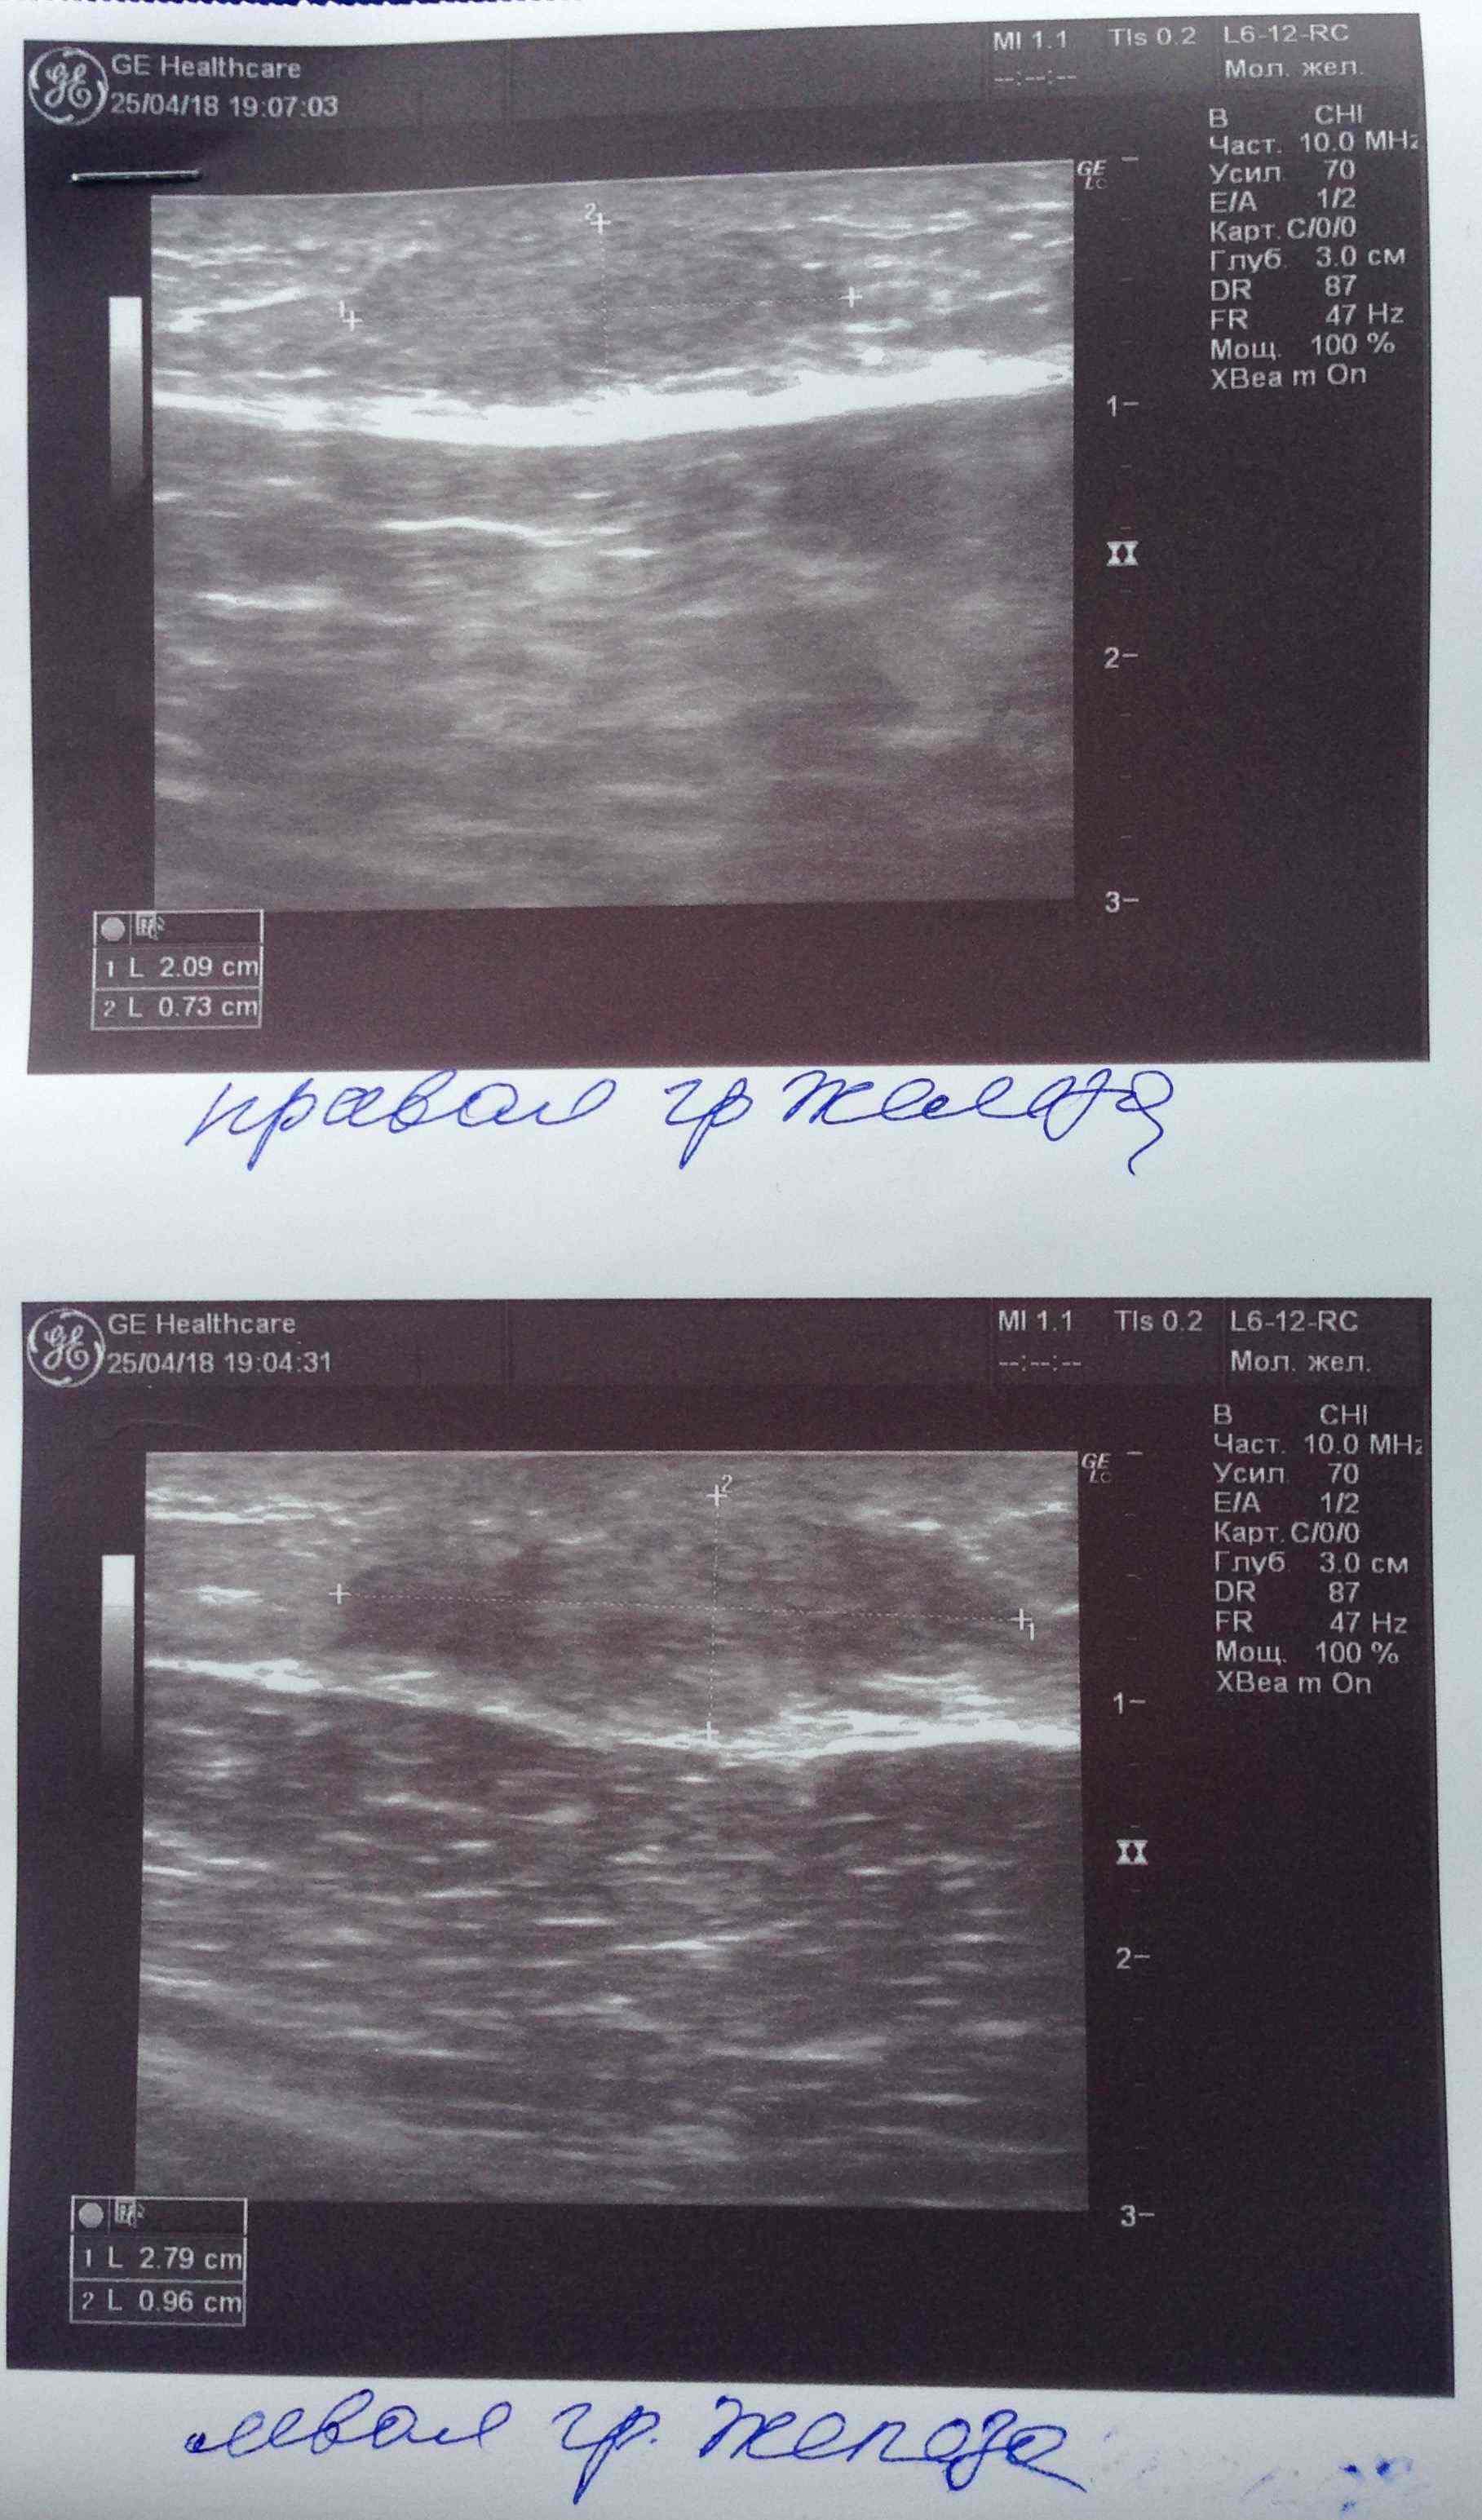

Ну да, железа увеличина.Посмотреть вложение 14714 Всем привет. Был курс нанфинил100+проп100. Набухли сиськи. Е2 и пролоктин в норме. PartyKill посоветовал сделать УЗИ .Результат: Эхо-признаки двусторонней геникомастии. Ну врачи привыкли всё драматизировать и слегка преувеличивать. Ну лечиться всё равно надо. Посоветуйте братья . До этого проблем с гино небыло.Может эта реакция на нанфинил такая? (Юзал первый раз)Хотя дека прошлым курсом нормально так вкатила.Стаж 4 года, ну разумеется с отдыхом , ПКТ, сдачей анализов. Всё по фэн-шую, всё как мы любим.Сейчас идёт мост , энка250 . Хотелось бы подлечиться а с июня снова в бой )) Выручайте